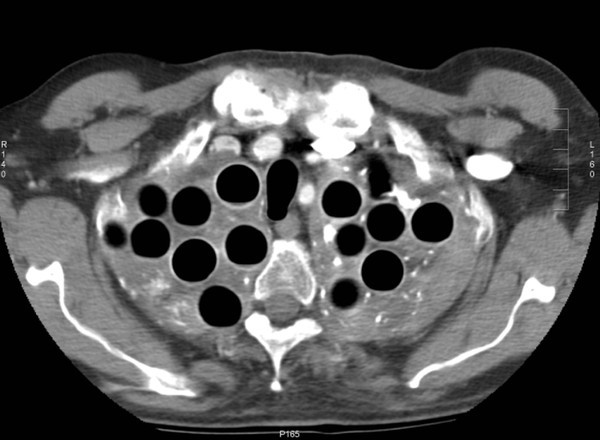

Đây là một biện pháp điều trị đầy mạo hiểm được sử dụng vào những năm đầu thế kỷ XX cho các bệnh nhân lao. Cụ thể, các bác sĩ sẽ tiến hành phẫu thuật với hai bước chính. Đầu tiên họ sẽ "đục" những lỗ nhỏ trong phổi bệnh nhân, rồi trám vào đó những… trái bóng nhựa.

151112med04-12a42

Theo lý thuyết vào thời này, các trái bóng nhựa sẽ giúp phần phổi bị nhiễm trùng tự lành trở lại. Tuy nhiên, đây chắc chắn là một phương pháp phản khoa học, vì chỉ có thuốc mới có thể diệt được khuẩn tuberculosis gây ra bệnh lao mà thôi.

151112med05-a4e70

Sau một khoảng thời gian áp dụng không hiệu quả, phương pháp này dần bị loại bỏ ở phần lớn các nước phát triển.